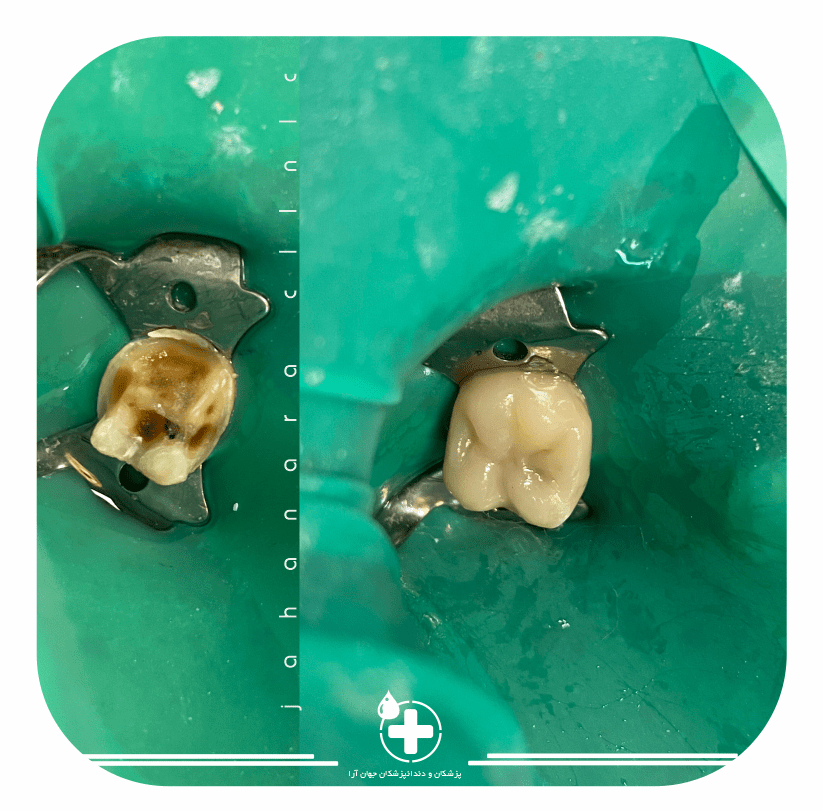

ترمیم همرنگ

ترمیم پوسیدگی همرنگ دندانقیافش مثل روز اول میشه

عصبکشی روتاری

عصب کشی با سیستم مدرن روتاریبالاترین سرعت و کمترین مشکلات

Root Canals

عصب کشی بدون درد و معتلی با سیستم اپکس و روتاری.